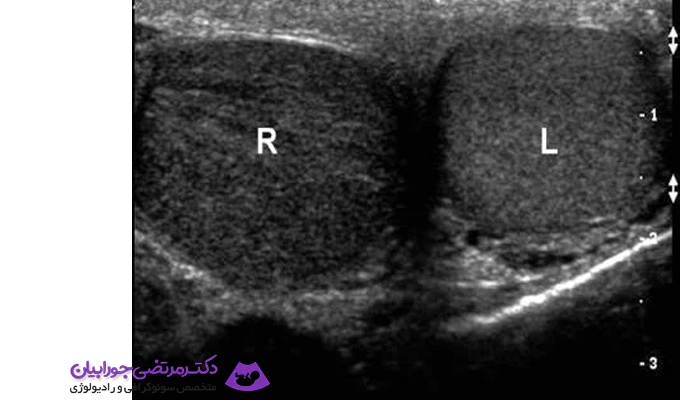

سونوگرافی بیضه یک روش تصویربرداری پزشکی غیرتهاجمی است که با کمک امواج صوتی با فرکانس بالا انجام می‌شود. این آزمایش بدون درد و بدون استفاده از اشعه انجام می‌گیرد و تصویر دقیقی از بیضه‌ها، اپیدیدیم و رگ‌های اطراف آن‌ها ارائه می‌دهد. پزشکان معمولاً از این روش برای بررسی مشکلاتی مانند درد، تورم، توده یا تغییرات غیرعادی در بیضه‌ها استفاده می‌کنند.

این آزمایش هم در کودکان و هم در بزرگسالان کاربرد دارد. اهمیت سونوگرافی بیضه در این است که به پزشک کمک می‌کند مشکلاتی مانند پیچ‌خوردگی بیضه، عفونت، واریس بیضه (واریکوسل) یا حتی توده‌های مشکوک به سرطان را تشخیص دهد. از آن‌جا که بسیاری از این مشکلات در صورت تشخیص زودهنگام قابل درمان هستند، انجام سونوگرافی می‌تواند نقش حیاتی در حفظ سلامت باروری و عملکرد جنسی داشته باشد.

یکی از مهم‌ترین بیماری‌هایی که با این آزمایش مشخص می‌شود، پیچ‌خوردگی بیضه است. این حالت یک اورژانس پزشکی محسوب می‌شود و اگر سریع درمان نشود، می‌تواند باعث از دست دادن بیضه شود. سونوگرافی کمک می‌کند جریان خون در بیضه بررسی شود و تشخیص فوری داده شود.

همچنین بیماری‌هایی مثل واریکوسل (واریس رگ‌های بیضه)، عفونت اپیدیدیم، کیست‌ها، توده‌های خوش‌خیم و سرطان بیضه با این روش قابل شناسایی هستند. در بیماران نابارور نیز گاهی سونوگرافی بیضه انجام می‌شود تا علت احتمالی ناباروری بررسی شود.